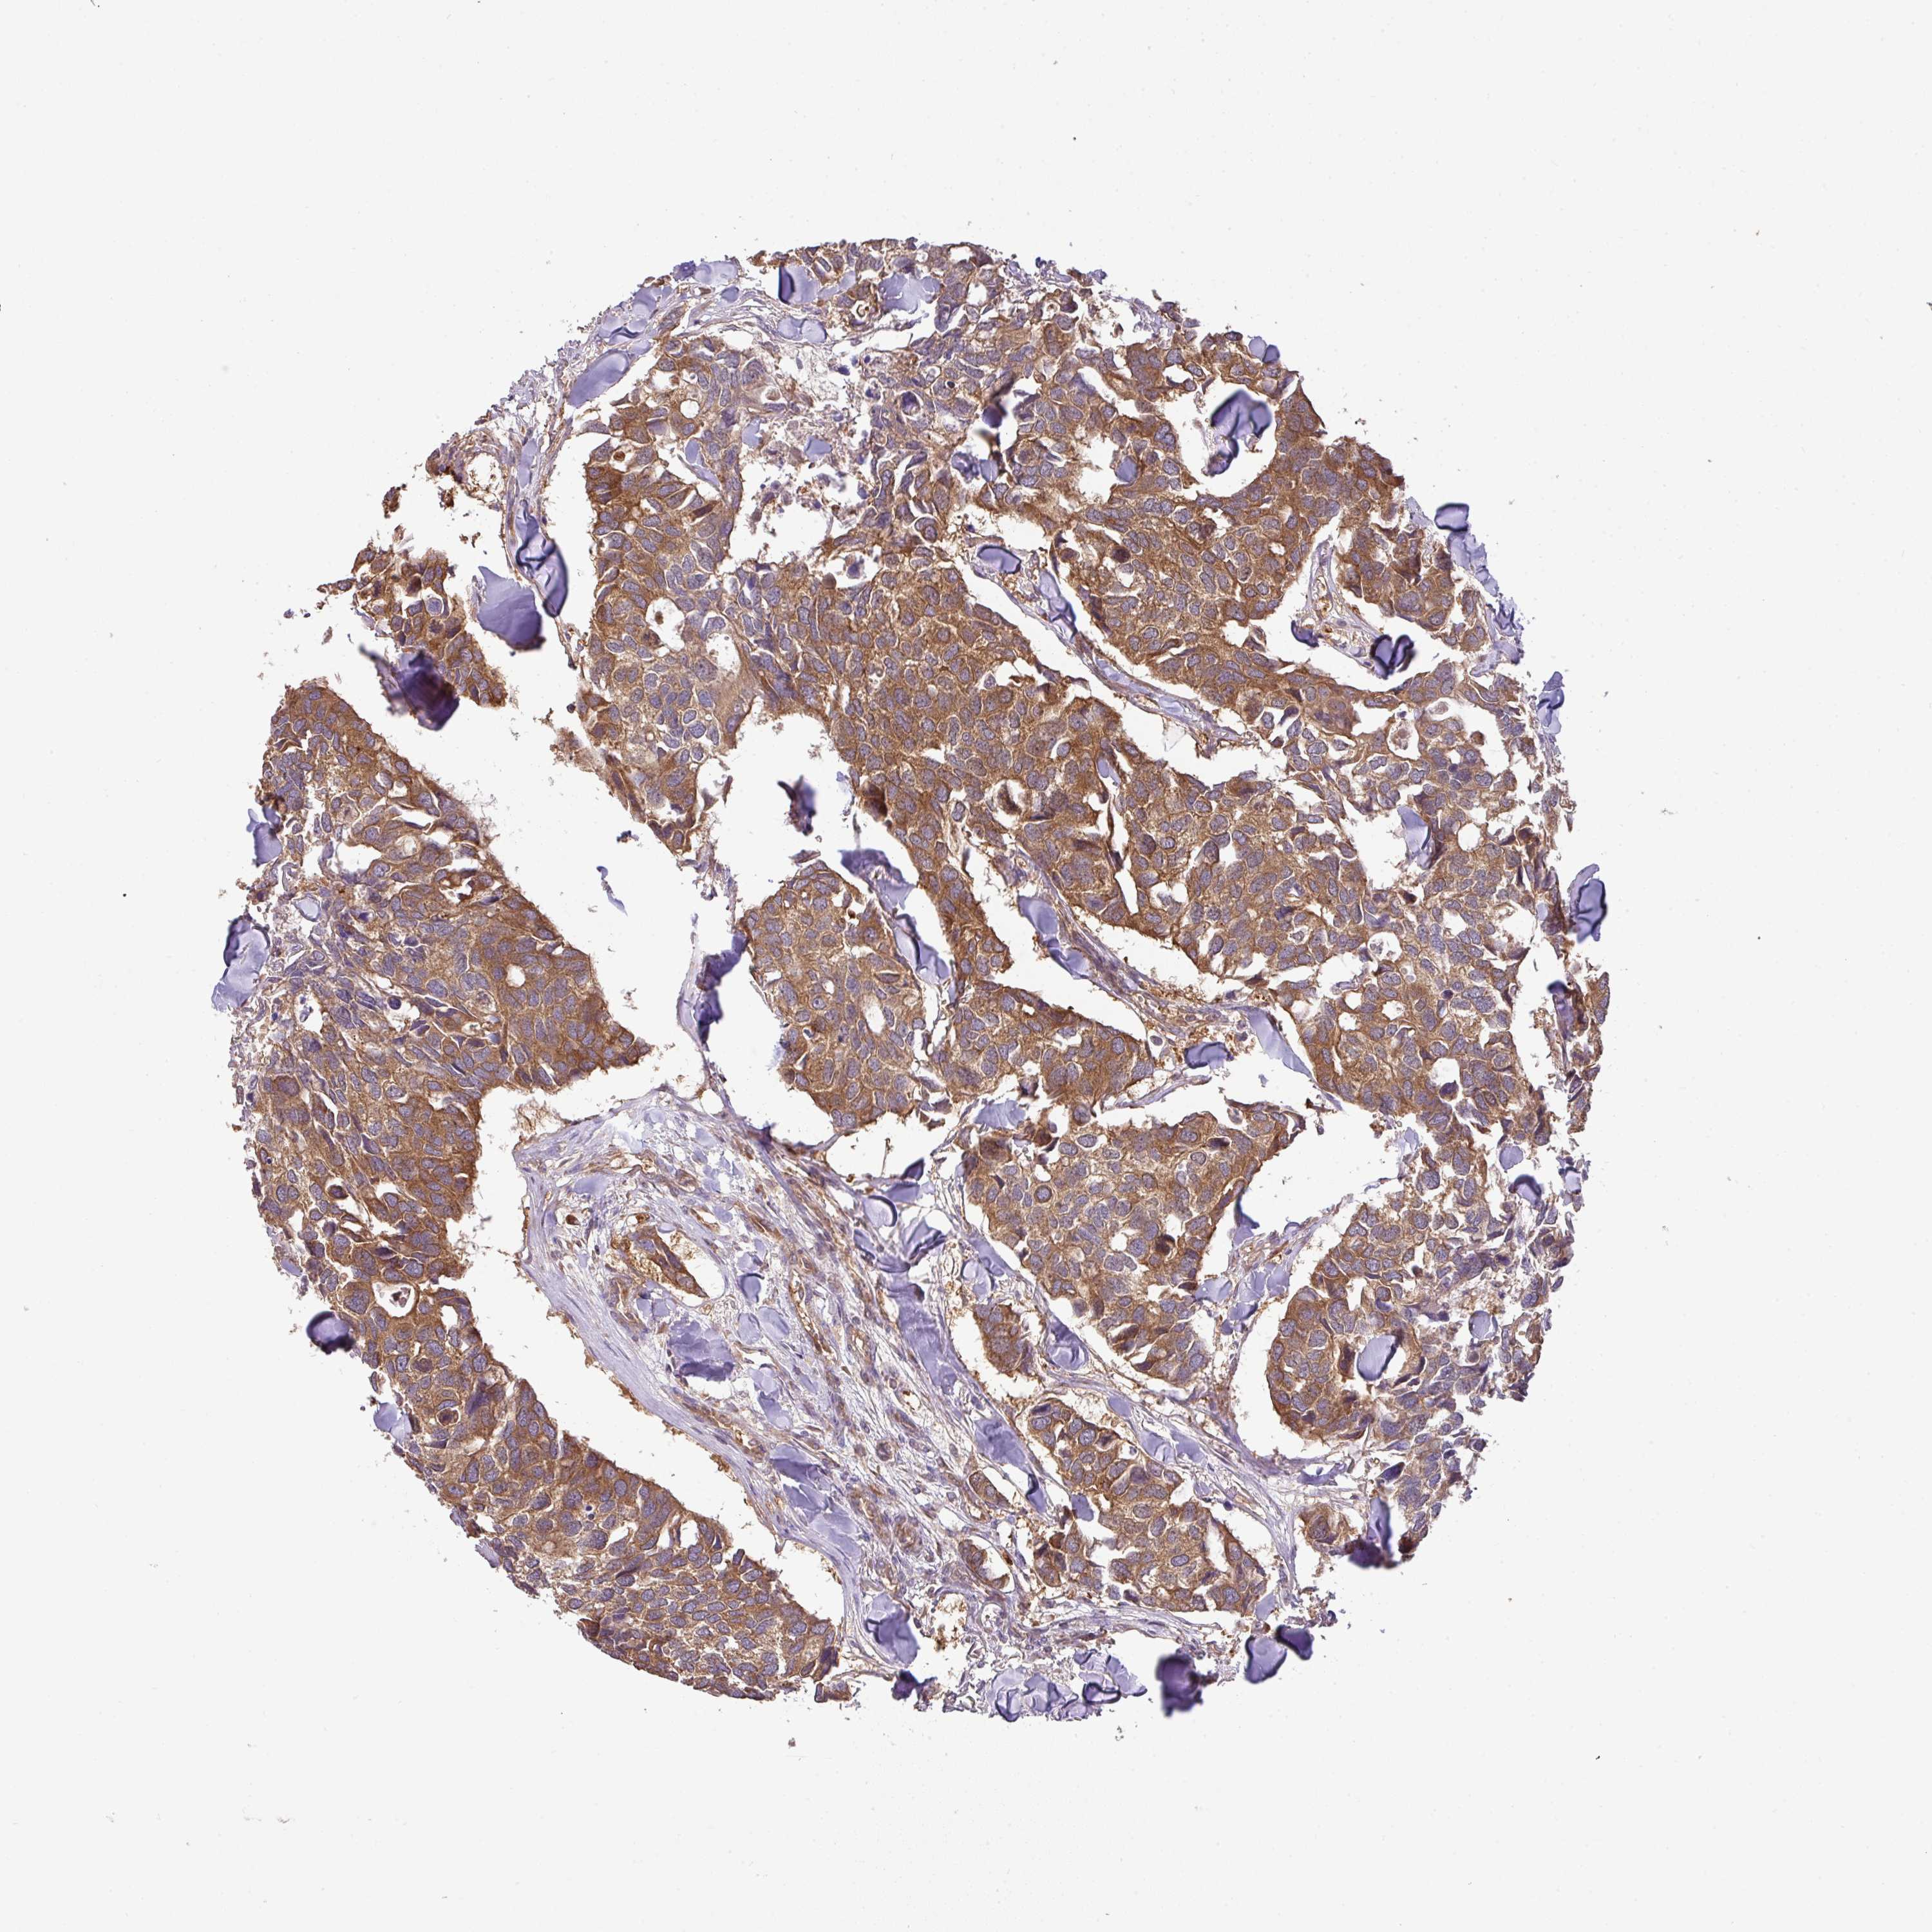

CANCER BREAST CANCER Show tissue menu

BRCA TCGA BRCA VALIDATION PROTEIN EXPRESSION